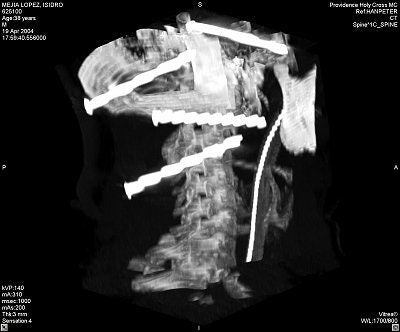

Quinonez was able to remove the nails based on the angiogram and 3D CT reconstructions that showed the location of the nail heads -- most critically, the head of a nail that had entered anteriorly through the base of the skull into the face and that now rested medial to the mandibular condyle (images C-E below).

![]() ![]() |

"There was concern as to (a nail's) relationship to several branches of the carotid artery," noted Greenberg. "The nail was going to be taken out from the left side of his neck, but the sharp end was on the right side, where the surgeon was not going to have access if something was going to start bleeding."